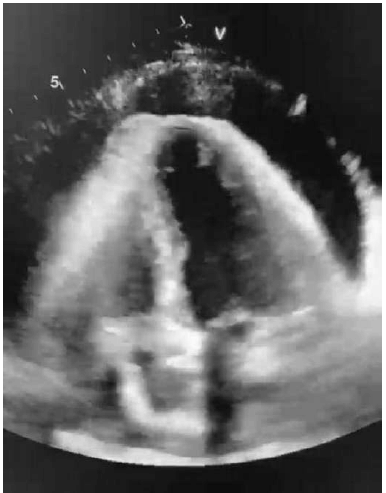

Uma paciente de 40 anos de idade chega ao pronto-socorro referindo ortopedia, edema de membros inferiores e dispneia aos pequenos esforços de início há cerca de 1 semana. Ao exame físico, apresenta-se dispneica, com extremidades frias, com palidez cutânea e com frequência cardíaca de 120 bpm; eletrocardiograma com padrão de baixa voltagem e alternância elétrica. Foi realizado ecocardiograma à beira-leito, conforme se vê na imagem abaixo.

Assinale a alternativa que indica a conduta mais adequada diante desse caso clínico.